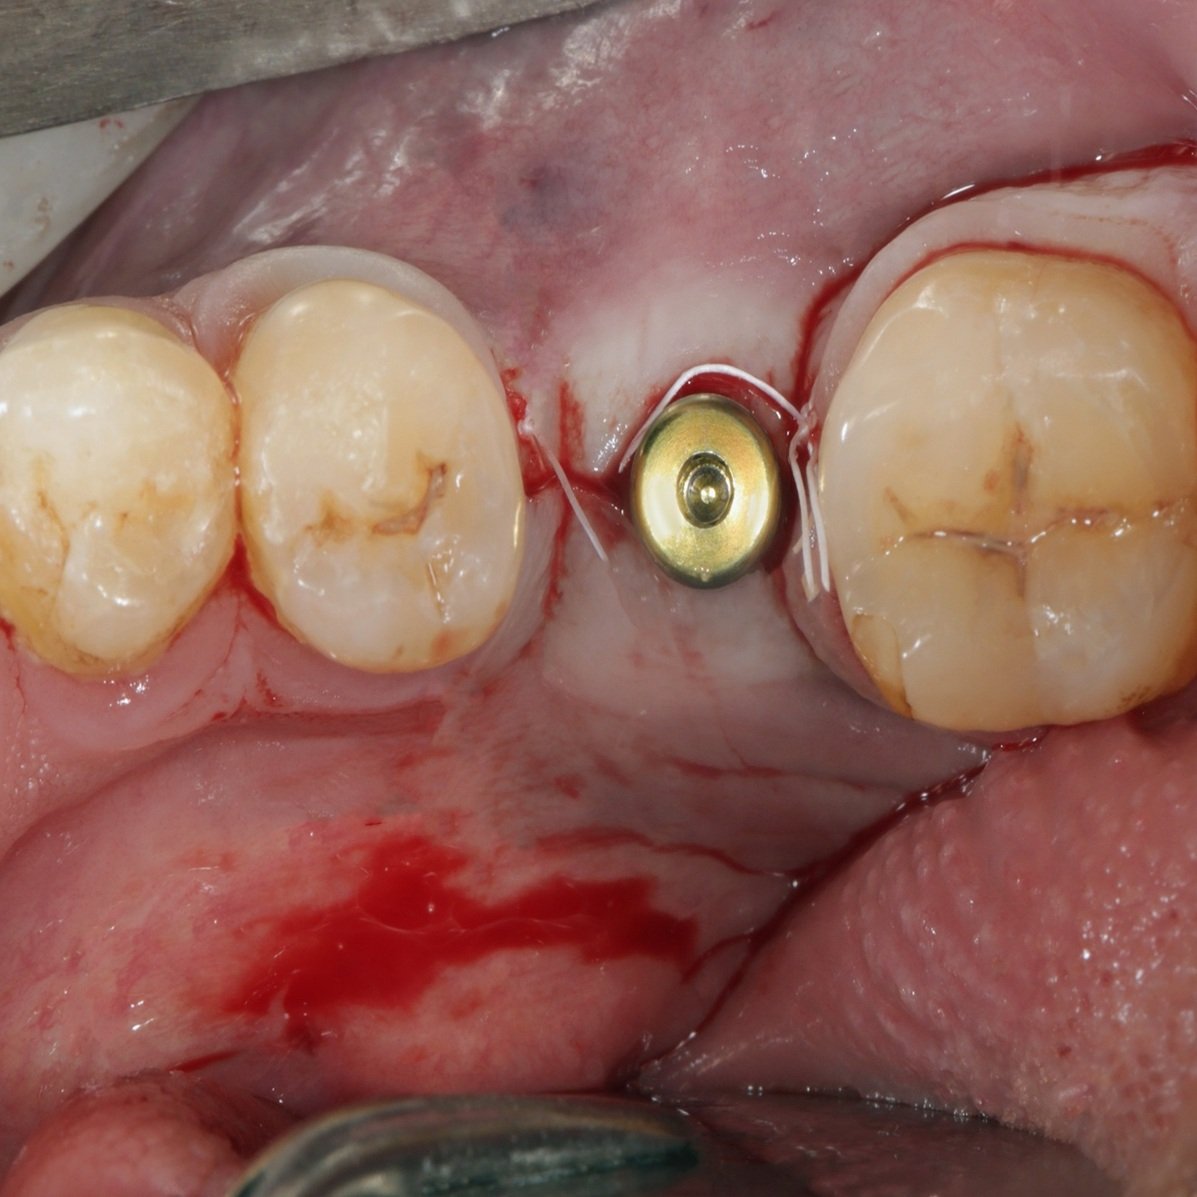

Dental implants are a revolutionary solution for replacing missing teeth, offering a permanent and natural-looking alternative to dentures or bridges. Designed to integrate with your jawbone, implants restore both function and appearance, allowing you to eat, speak and smile with complete confidence.

Dental implants are small titanium posts placed into the jawbone to replace missing tooth roots. They support crowns, bridges or full arch restorations.

The procedure is carried out under local anaesthetic to ensure comfort. Mild discomfort during healing is normal and manageable.

Gallery

Take a Look Inside Our Clinic

Every face tells a story. Explore real treatment outcomes achieved at Reform Aesthetics and Dental. If you’re considering dermal fillers and would like to discuss your goals, book a personalised consultation with our team.